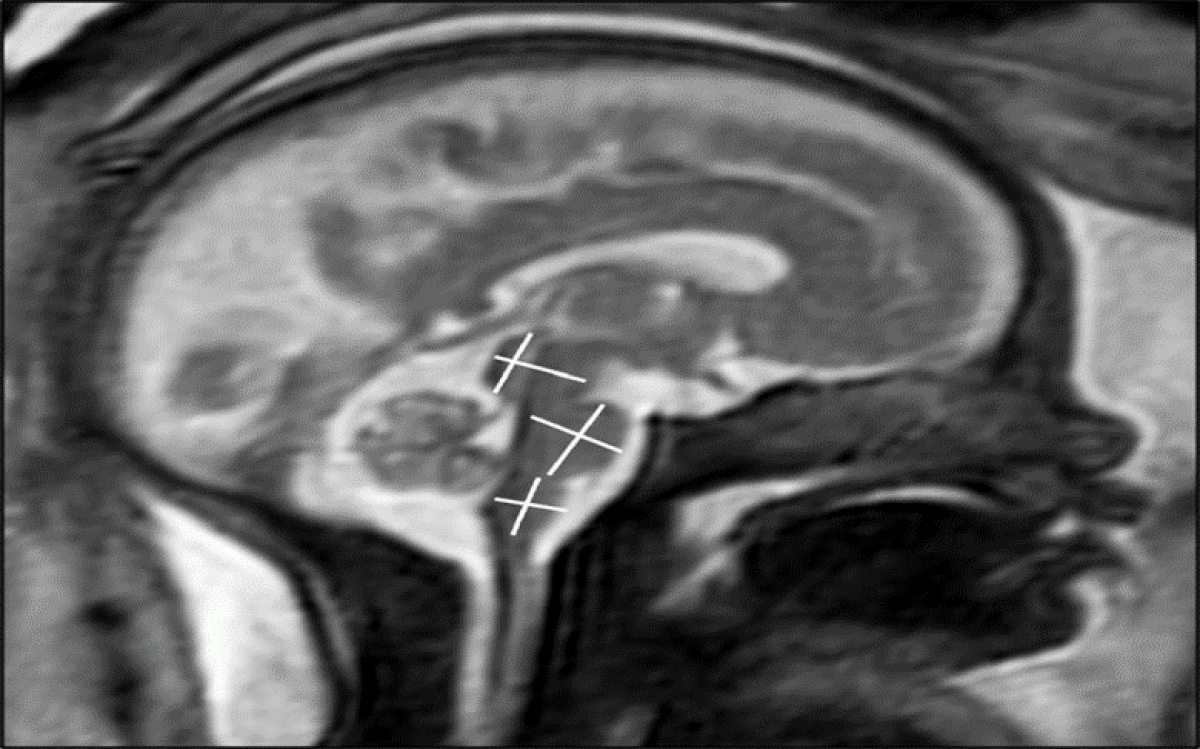

Chụp MRI chẩn đoán sự phát triển não bộ của thai nhi. (Ảnh: RSNA và Tiến sĩ Sophia Stöcklein)

Các nhà nghiên cứu đã chụp MRI thai nhi (chụp cộng hưởng từ thai nhi) cho 33 bệnh nhân nhiễm COVID-19 trong thai kỳ. Trung bình, các bệnh nhân mang thai được khoảng 28 tuần, và các triệu chứng khởi phát khi họ mang thai hơn 18 tuần. Các triệu chứng phổ biến nhất của các bà mẹ là mất hoặc giảm khứu giác và vị giác, ho khan, sốt và khó thở.

Theo kết quả nghiên cứu, sự phát triển não bộ ở những khu vực được đánh giá là phù hợp với độ tuổi ở tất cả các thai nhi. Không có phát hiện nào cho thấy não của thai nhi bị ảnh hưởng.